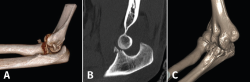

Fractura de Monteggia y lesiones Monteggia-like

Son lesiones poco frecuentes pero complejas. Es esencial una reconstrucción anatómica precisa del cúbito proximal para recuperar la funcionalidad del codo. La restauración anatómica de la longitud y las dimensiones del cúbito será crucial para la congruencia de la articulación radiocapitelar. Una reconstrucción fallida o inadecuada acabará con dolor persistente y una progresiva degeneración de la articulación. Hay que poner especial atención en 2 fragmentos: la faceta anteromedial de la coronoides y la faceta anterolateral del cúbito, junto a la cresta del supinador. La planificación preoperatoria es vital, por lo que recomendamos la TAC con reconstrucción 3D (Figura 9).

Figura 9. A: imagen en 3D de una fractura proximal compleja de cúbito y radio; B y C: radiografías de control tras la cirugía en otro caso de lesión Monteggia-like.